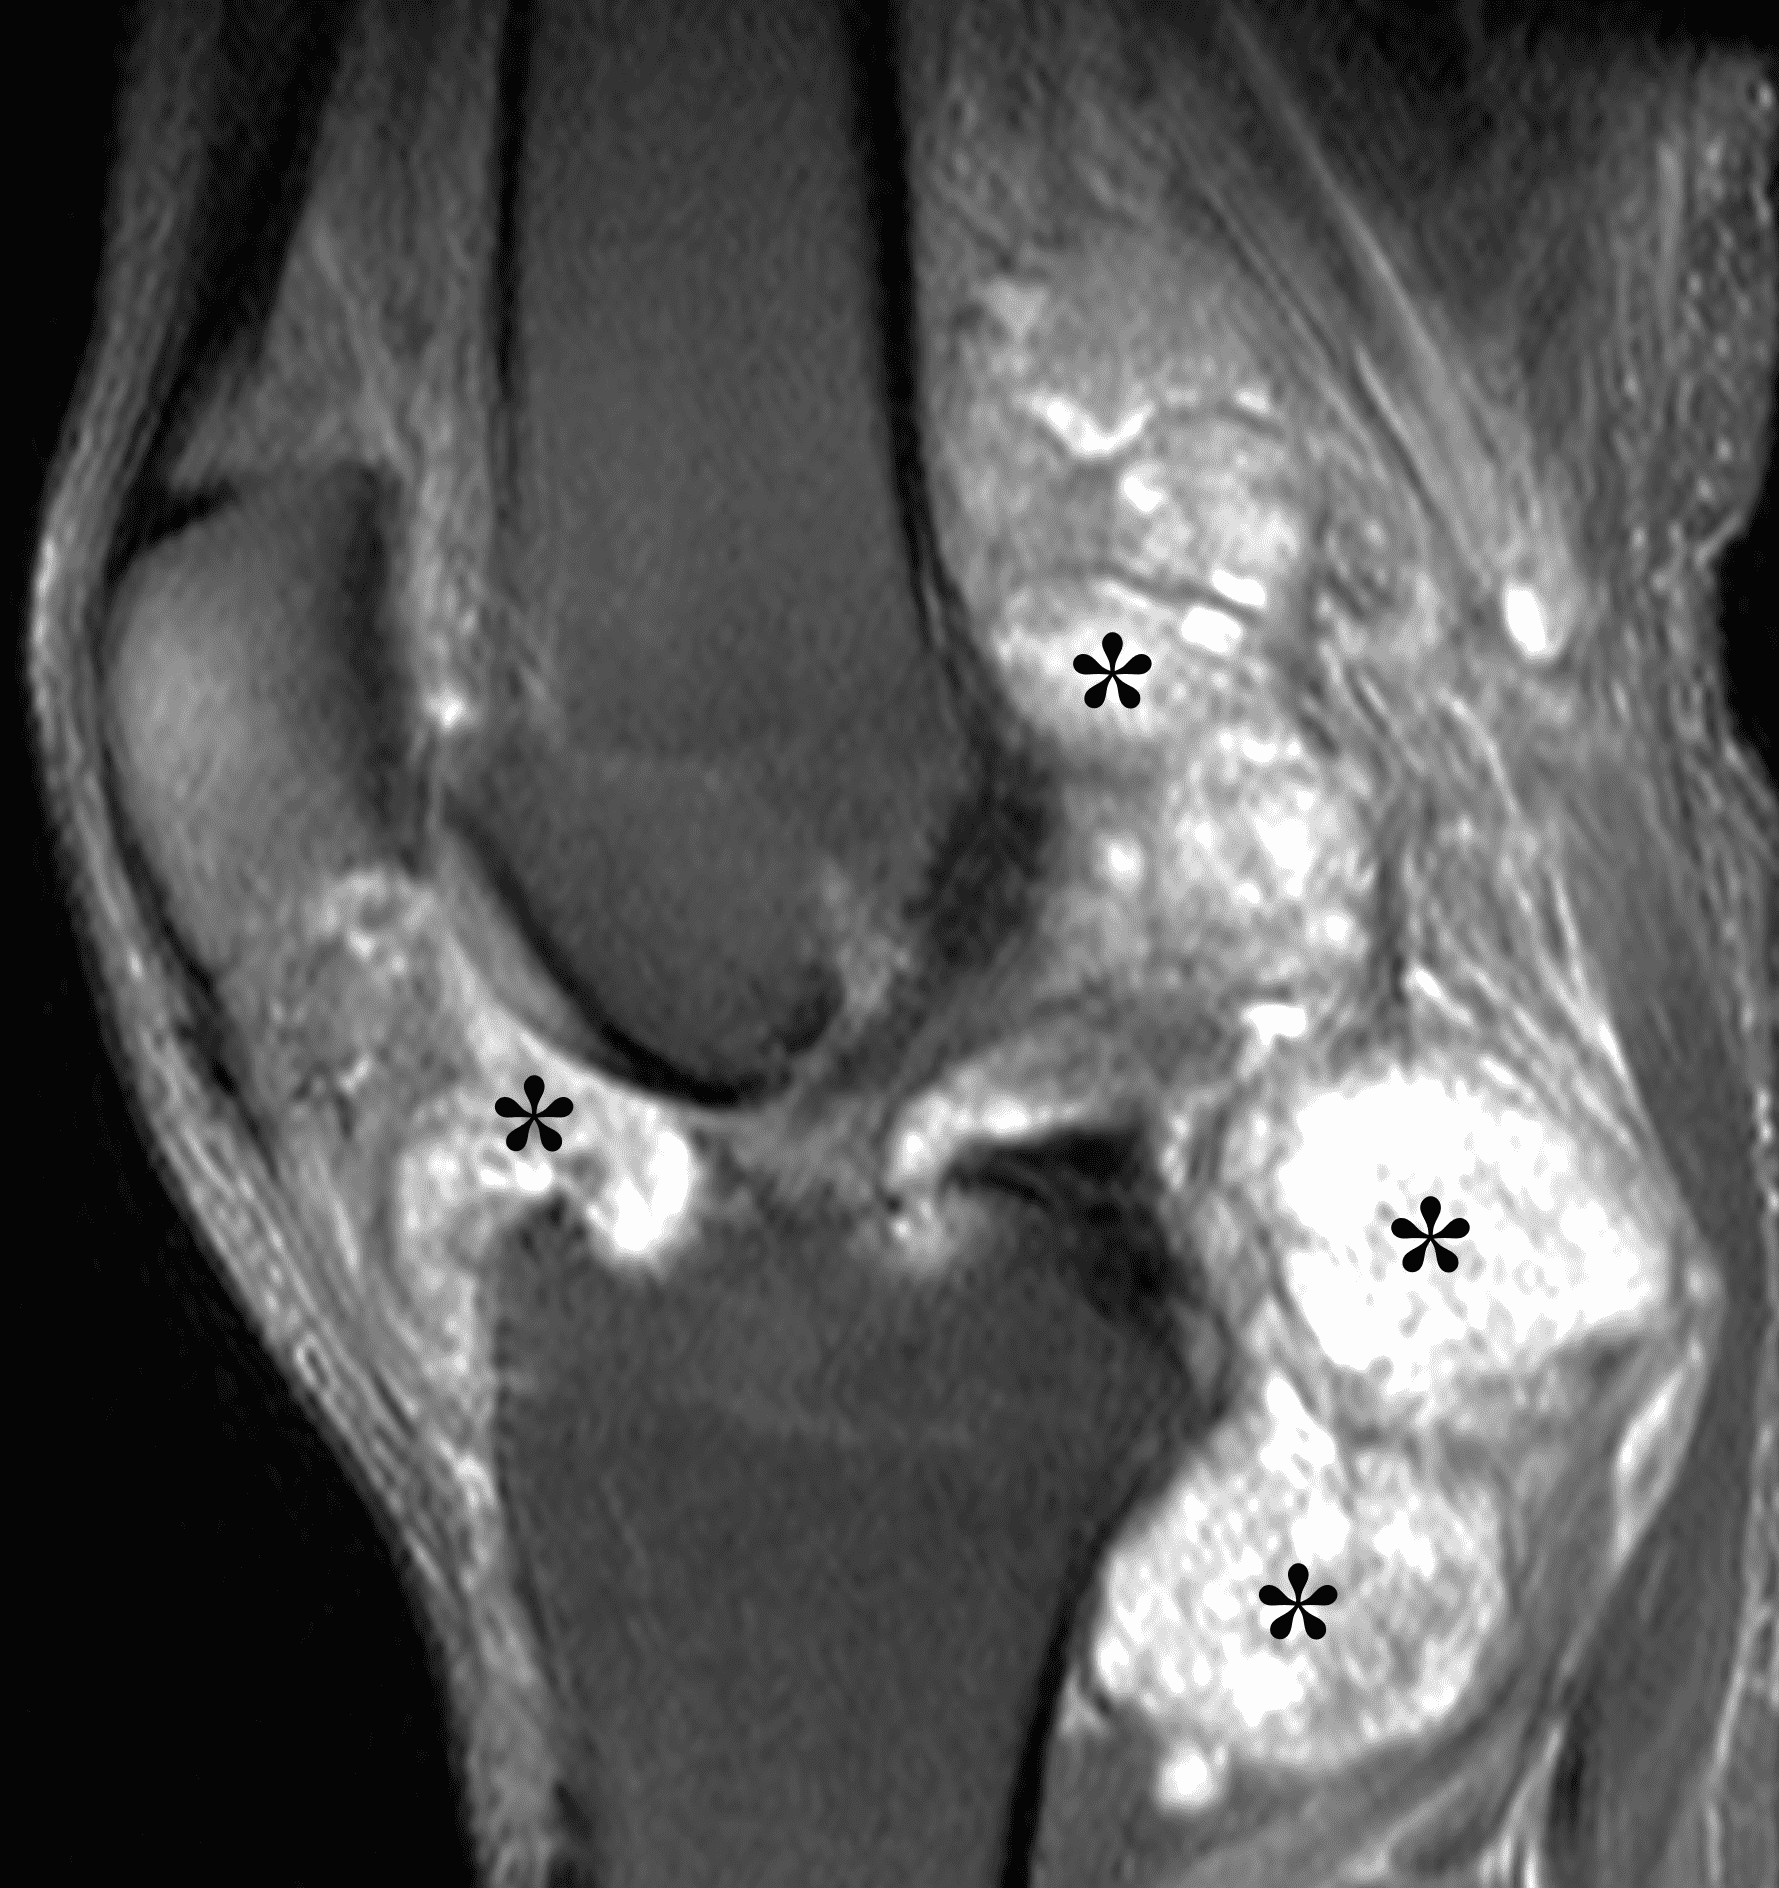

Figure 3: Diffuse type tenosynovial giant cell tumor in the knee. (3A) Sagittal fat-suppressed T2-weighted, (3B) sagittal proton density-weighted, and (3C) coronal T1-weighted images demonstrate diffuse mass-like synovial proliferation in the anterior and posterior joint space including the suprapatellar recess, with intermediate-to-hypointense signal on all pulse sequences (asterisks). Very low signal intensity foci represent hemosiderin deposition (arrows). (3D) A sagittal gradient echo localizer image shows “blooming” artifact from the hemosiderin (arrows).